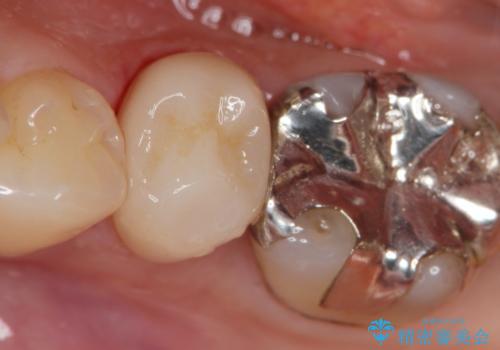

神経を保存できるよう丁寧に虫歯を除去し、セラミックによる機能回復を計画します。

- 8万円(仮歯・エコノミーemaxクラウン)費用は治療当時の料金となります

- 天然歯を削ります

- 硬い素材は天然歯を傷つけてしまう場合があります

- かみ合わせや歯ぎしりが強すぎる方はセラミックが割れてしまう可能性があります

- 自費診療(保険適用外治療)となります